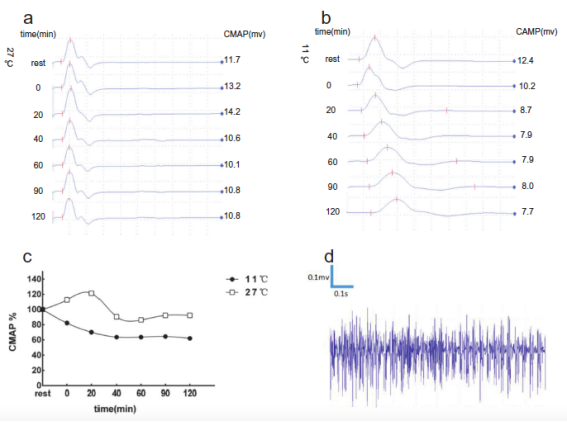

另一个家系中部分成员被诊断为SCN4A基因突变(R1448H)所致先天性副肌强直合并低钾型周期性麻痹2型�����。此外����,在此家系中一位具有重叠症状的患者为SCN4A基因T704M突变而非R1448H突变����。